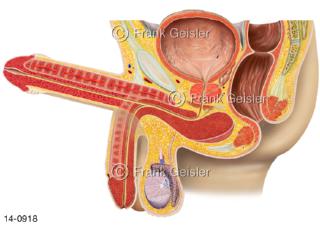

Bildergalerie Urogenitalsystem

Bilder zum Urogenitalsystem mit Urogenitalorgane, Urogenitaltrakt, zum Harn- und Geschlechtsapparat, Harnorgane und Geschlechtsorgane, Organe der Harnwege und der Fortpflanzung, Harnorgane und Geschlechtsorgane im männlichen und weiblichen Urogenitalsystem